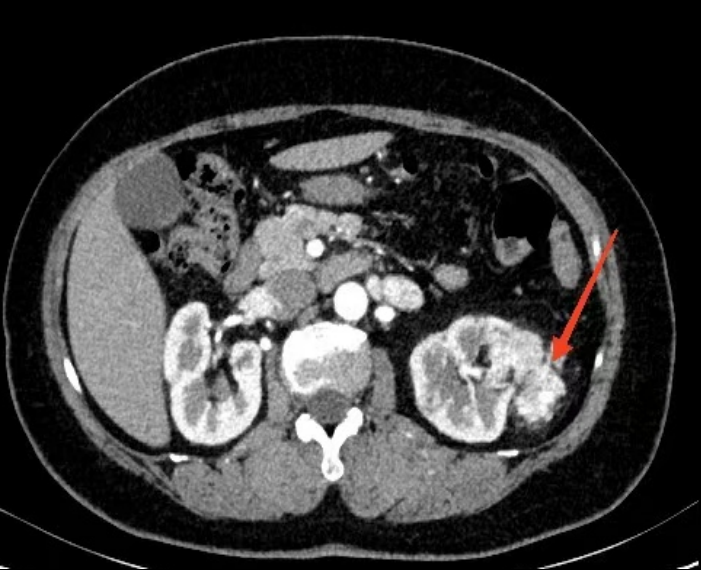

3个月前患者于体检中发现左肾占位性病变,行增强CT检查提示左肾上极存在一个约12cm×4cm的不规则肿物,双肾动脉成像进一步明确为血管平滑肌脂肪瘤。患者暂无症状,为求进一步诊治入院。

增强CT:左肾上极可见约12cm×4cm不规则肿物,增强后呈不均匀强化,双肾动脉成像提示肿物为血管平滑肌脂肪瘤。